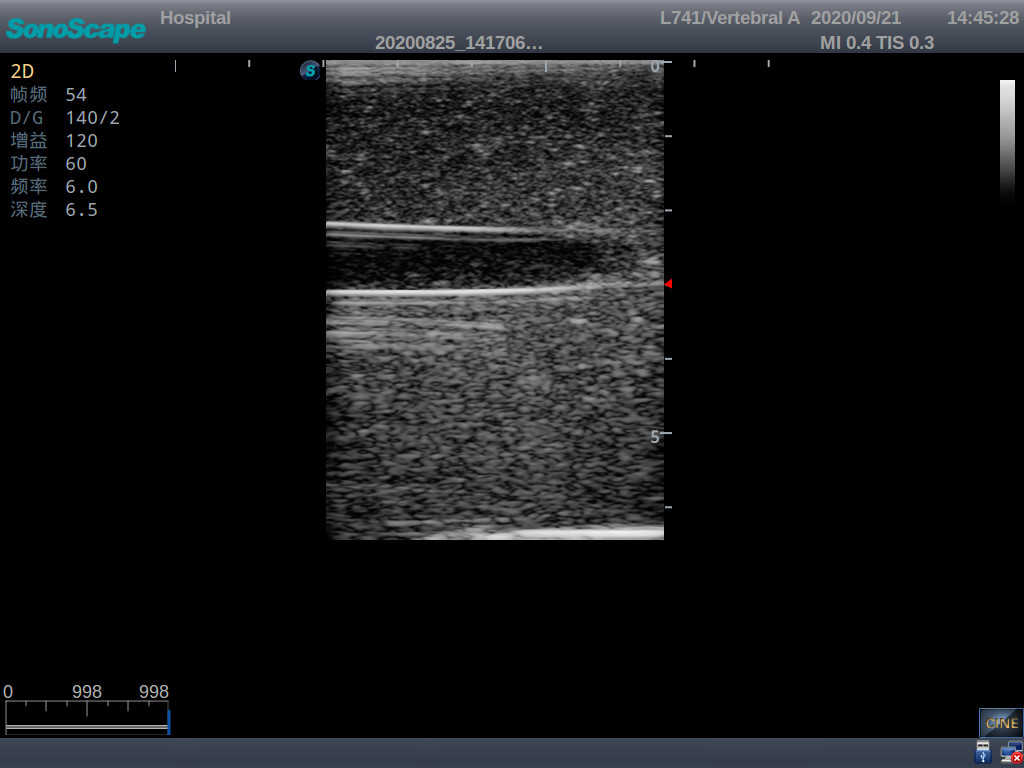

Vascular Access Ultrasound Training Model

Model TYE4034

The model is designed for simulating skin and arteriovenous puncture. It contains an artery and a vena comitans. Trainees can practice arteriovenous identification, arteriopuncture and venipuncture.

1) Made of high molecular polymer ultrasound material, close to real skin. It can conduct ultrasound-guided puncture exercises with various clinical models of real ultrasound machines

2) Clear and real images of arteries and veins

3) Showing physiological phenomena that veins are easier to be flatted than arteries under external pressure